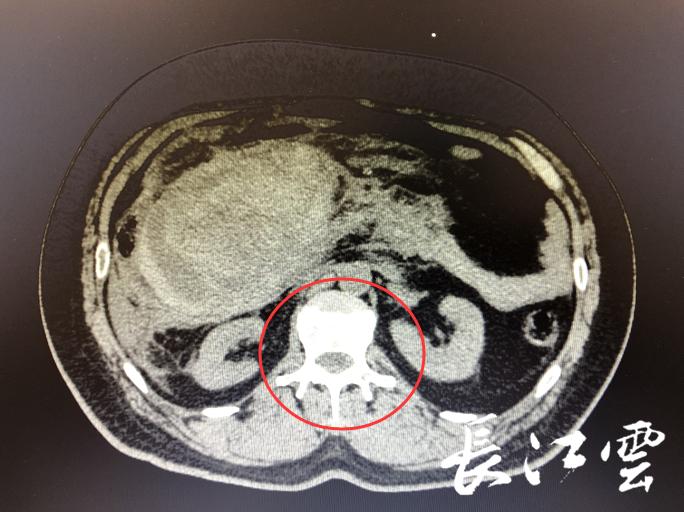

孙先生腹膜后15*8*20cm的巨大血肿

术前检查显示,孙先生体内每毫升血液的血红蛋白仅为5克,而正常人为12克,在没有其它病症的情况下,也就表示,他的失血量已经超过全身血量的一半了。”李明杰主任说,加上CT检查显示,患者的腹腔、盆腔、腹膜后大量积液,这些都表示,孙先生的腹腔大量出血,且全部积于腹部。